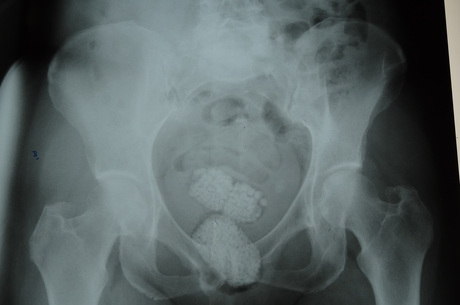

Um casal de estrangeiros foi preso ontem (24) em flagrante, no Aeroporto Internacional Tancredo Neves, em Confins, na Grande BH, após serem flagrados tentando embarcar para a Europa com grande quantidade de pedras de diamantes. A mulher, uma idosa belga, de 64 anos, identificada como Schoshana Handfuchs, escondia 102 gramas da pedra em estado bruto dentro do absorvente nas partes ítimas. Os agentes descobriram ainda, após radiografia realizada no Hospital João 23, em BH, que ela escondia duas porções da pedra na região do reto.